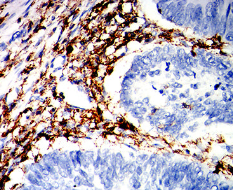

CD162 Mouse Monoclonal antibody[3D5E1]

IHC    1/200 - 1/1000